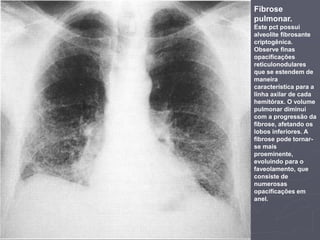

Fibrose

pulmonar.

Este pct possui

alveolite fibrosante

criptogênica.

Observe finas

opacificações

reticulonodulares

que se estendem de

maneira

característica para a

linha axilar de cada

hemitórax. O volume

pulmonar diminui

com a progressão da

fibrose, afetando os

lobos inferiores. A

fibrose pode tornar-

se mais

proeminente,

evoluindo para o

faveolamento, que

consiste de

numerosas

opacificações em

anel.